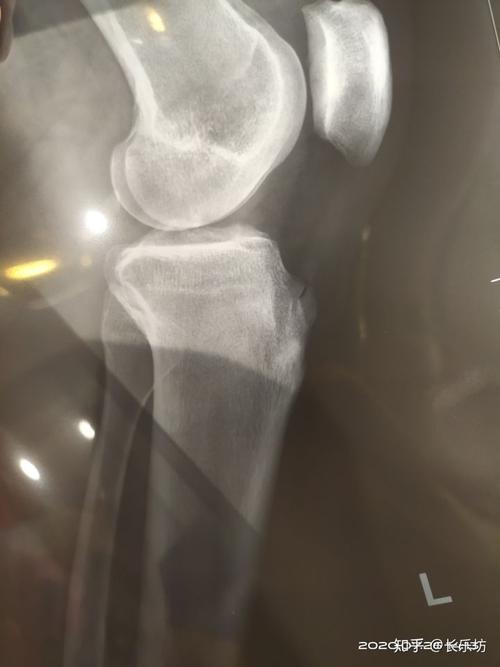

膝盖骨骨折

膝盖骨头

膝盖骨裂